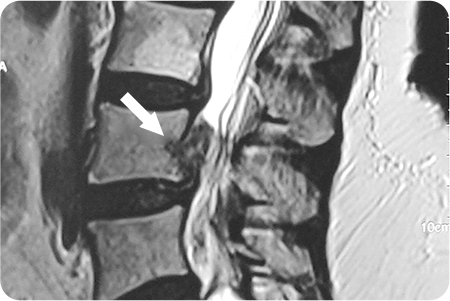

1

관절경하

척추디스크 제거술

1cm 내외 절개를 통해 내시경을 삽입해

디스크가 신경을 누르는 부위를 직접 확인합니다.

튀어나온 디스크 조각을 특수 기구로 제거해

신경 압박을 풀어줍니다.